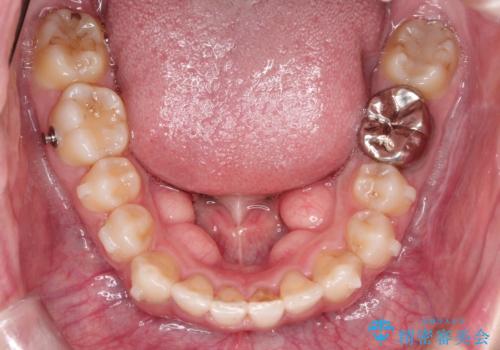

奥歯を後方に移動することで、歯を抜かずに矯正を終えることができました。